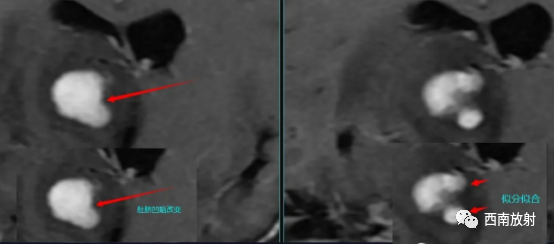

▲病例:脑淋巴瘤。脑深部结节病灶,具有刀切征、凹陷征或肚脐凹征、尖角、多发。DWI呈稍高信号,形态上怪异,波普NAA及Cho减低,出现导致LL峰。颈部、胸廓入口区及腋窝多发淋巴结肿大并相互融合。